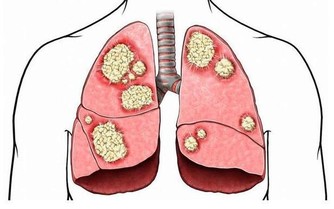

*****2、病毒侵犯心臟****

即便是身體健壯,若是出現流行性感冒或者是病毒性腹瀉,那麼就要當心了,因為這一部分患者中約有4%的人會被病毒侵犯心臟。如果還連續熬夜,過度疲勞,免疫力還會下降,就更容易被病毒侵犯。

一旦病毒侵犯心臟傳導系統,那麼可會引起嚴重心律失常,嚴重的甚至室顫,最終猝死。